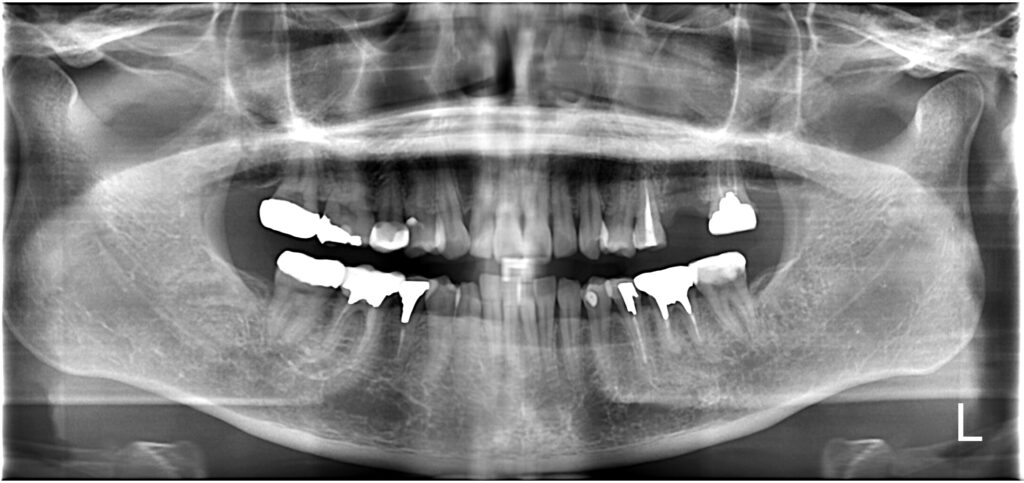

【A様】

パノラマ①

年齢 | 30代後半 |

性別 | 女性 |

主訴 | 歯を抜いた後、周りの歯を削ることなく噛めるようにしたい |

施術内容 | 右上第一大臼歯欠損部にインプラントを埋入し、ジルコニアクラウンを被せてあります |

治療期間 | 約1年(抜歯からジルコニアクラウン装着まで) |